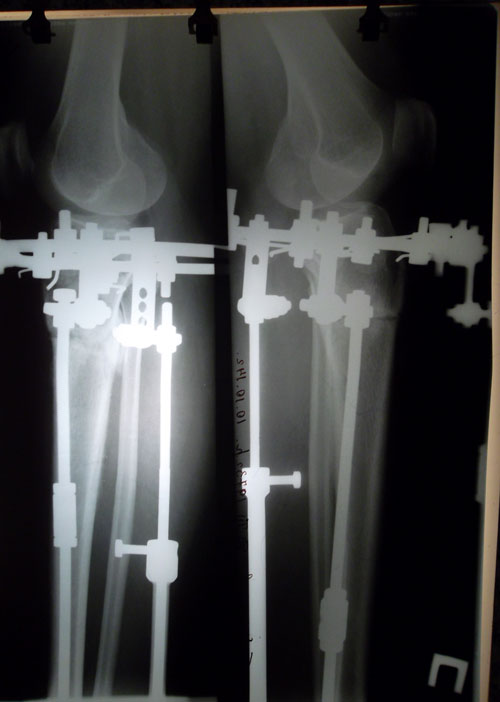

Дата операции 01.07.2014г.

Дата снятия аппаратов 17.10.2014г.

Срок лечения 97 дней.